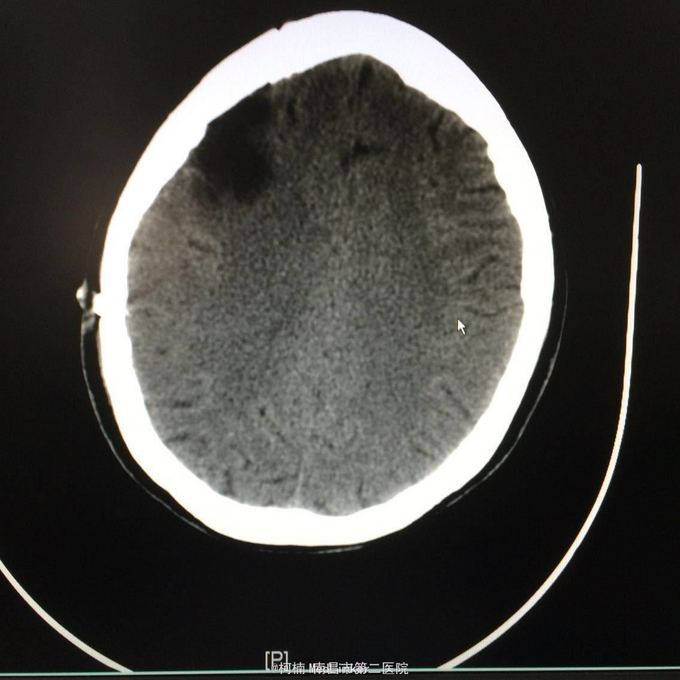

主诉:头痛2年,加重2月 病史:2年前无明显诱因出现头痛,主要为右侧额颞叶胀痛,近两个月来上述症状加重,遂至当地医院行头颅CT提示:右侧额颞叶类圆形异常信号,考虑脑膜瘤合并出血。

神经系统查体阴性 辅助检查:头颅CT提示右侧额颞骨板下肿物伴瘤卒中考虑脑外源性脑膜瘤